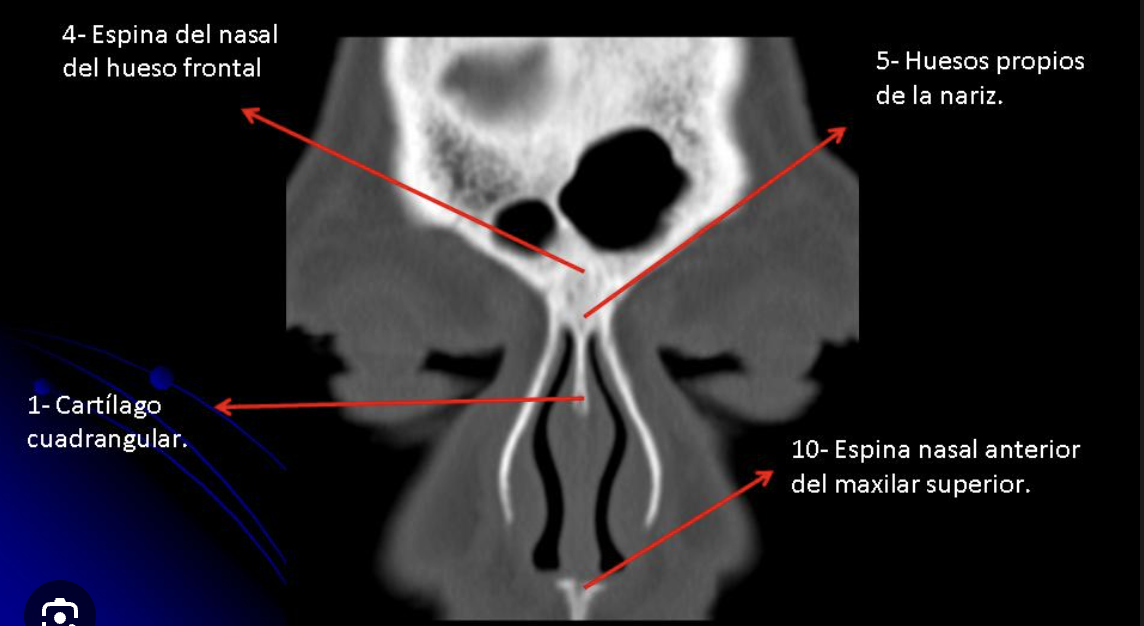

Q

¿Qué importancia tiene la espina nasal en TC?

A

Tiene forma de “Y” y sirve como base donde reposa el cartílago del septum nasal

How well did you know this?

1